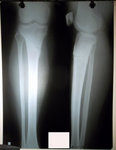

рентген в 20 дней с момента операции.

Сращение идёт отличное, как у 16 летней девочки!